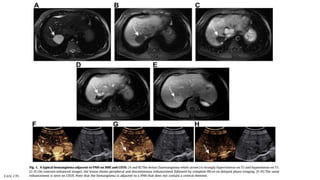

Hemangioma

A, Hemangioma. Ultrasonography demonstrates

a large circumscribed uniformly hyperechoic

mass in the right hepatic lobe

B, Ultrasonography demonstrates atypical hypoechoic

appearance of a large hemangioma (in the setting of an

echogenic liver due to hepatic steatosis).

Hepatic haemangiomas: imaging

EASL CPG benign liver tumours. J Hepatol 2016;65:386–98

T2 T1 CE

Typical haemangioma adjacent to FNH

MRI

CEUS

CE CE

Strongly

hyperintense

Hypointense Lesion shows peripheral and discontinuous enhancement followed by

complete fill-in on delayed-phase imaging